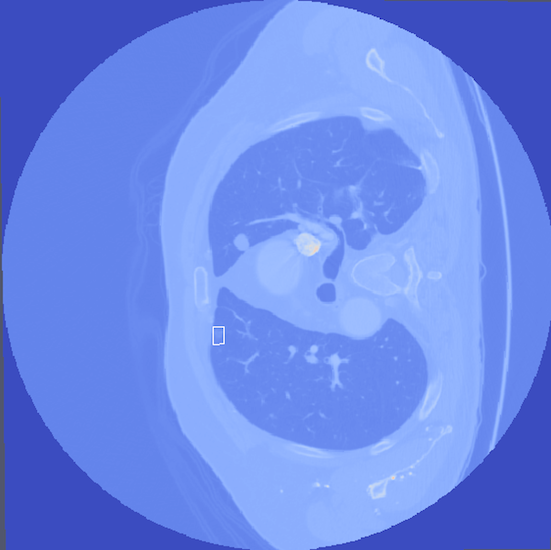

- Abstract: An exploration of whether conventional detection methods of lung cancers in low dose spiral CT scan could be improved using curvature features. In general, a large source of inaccuracy in detection rates can be attributed to irrelevant anatomical structures such as blood vessels. Often these irrelevant anatomical structures have different shape characteristics from lung nodules. For example lung nodules tend to appear bloblike as oppose to blood vessels, which appear cylindrical, or organ walls, which appear planelike. These curvature features were determined using eigenanalysis of the local second order image Hessian of each voxel, where the principal values are indicative of the local shape and provide more information than analysis performed on first derivatives alone.

- Method Overview: In each CT scan, the internal 3D lung volume was isolated using standard thresholding of pressurevalues ranges associated with lung parenchyma. The remaining voxels were conjoined using a connected components method, implemented through a union-find method, with small and isolated components removed. The remaining gaps were filled in using a standard 3D image closure method. First and second order partial derivatives were computed using Deriche filters, chosen for their stability and suitability in medical image scans. Then, for each of the voxels in the internal volume of the lung the local second order Image Hessian was generated and analyzed for preferred directions using eigenanalysis. This information was then used to weight the contribution of each voxel to standard lung nodule detection methods, to determine if giving stronger weight to voxels with local blob-like shape improved detections results.

Top row: An image slice demonstrating the lung Isolation process, enacted on a low dose spiral CT scan taken from the LIDC-IDRI database.

Bottom Row: Examples of lung nodule detections.